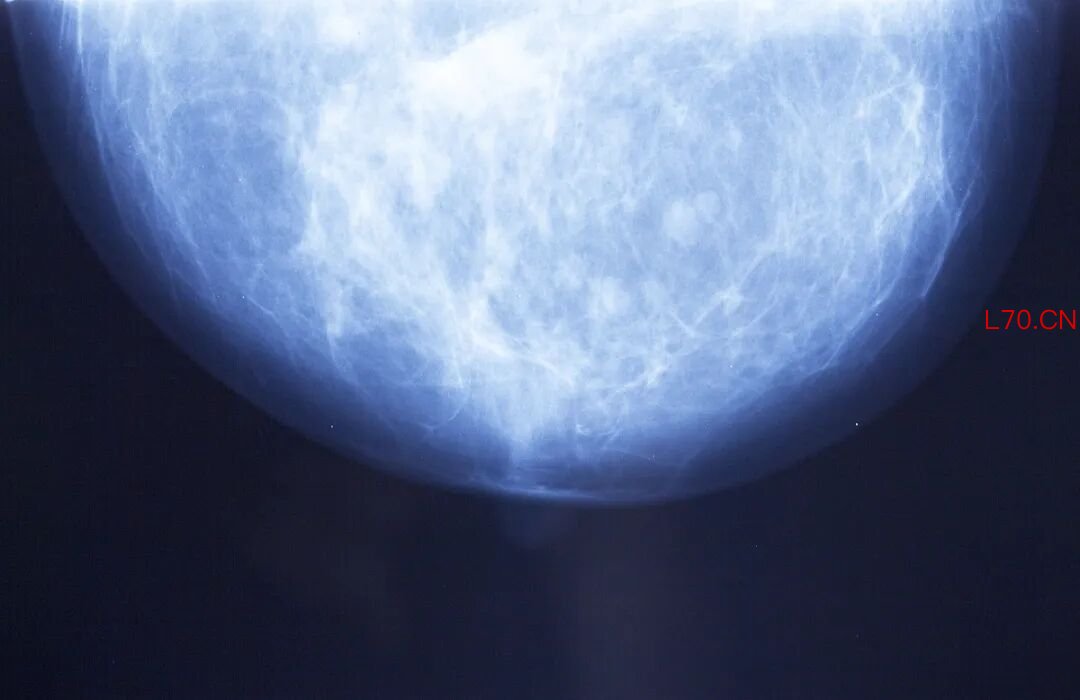

为了了解乳腺癌是如何在转移灶组织肿块生长的,研究人员收集了人类乳腺癌的原发灶、转移灶(包括脑、肝、皮肤)以及正常乳腺组织样本,并展开转录组分析。

既然不同亚型乳腺癌转移灶中的癌细胞都启动了FMM程序,那转移灶的三维结构肯定也是有特定组织的。借助于AI驱动的3D成像技术,研究人员重建了转移灶的三维形状和微观结构。果不其然,在不同组织器官的转移灶中,转移性乳腺癌细胞形成了一个三维晶格状结构。重要的是,这种结构并非由组织器官微环境所致,而是转移性乳腺癌的内在能力。

既然如此,那转移风险高的原发灶应该也存在小梁状结构。研究结果显示,所有预期会发生转移的原发肿瘤均呈现出与远处转移灶相似的小梁状结构,而非转移性原发肿瘤则保持着致密、实性的结构。